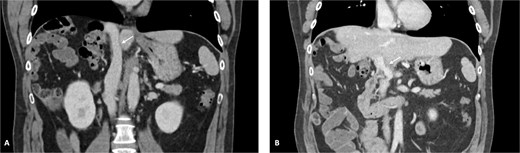

The post-operative period was complicated by bleeding from the left epigastric artery at the APFP harvesting site on post-operative day 14, requiring reintervention and vessel ligation. The patient was discharged on post-operative day 31. Pathology confirmed an ypT4G2N1R0 small-duct intrahepatic cholangiocarcinoma. No post-operative thrombosis or clinically significant stenosis were identified. Figure 6 demonstrates the reconstructed vessels 1 year after surgery. After completing 6 weeks of therapeutic low-molecular-weight heparin (LMWH), the patient continued rivaroxaban 20 mg once daily.

Reconstructed IVC and PV. (A) IVC and (B) PV 1 year after surgery.